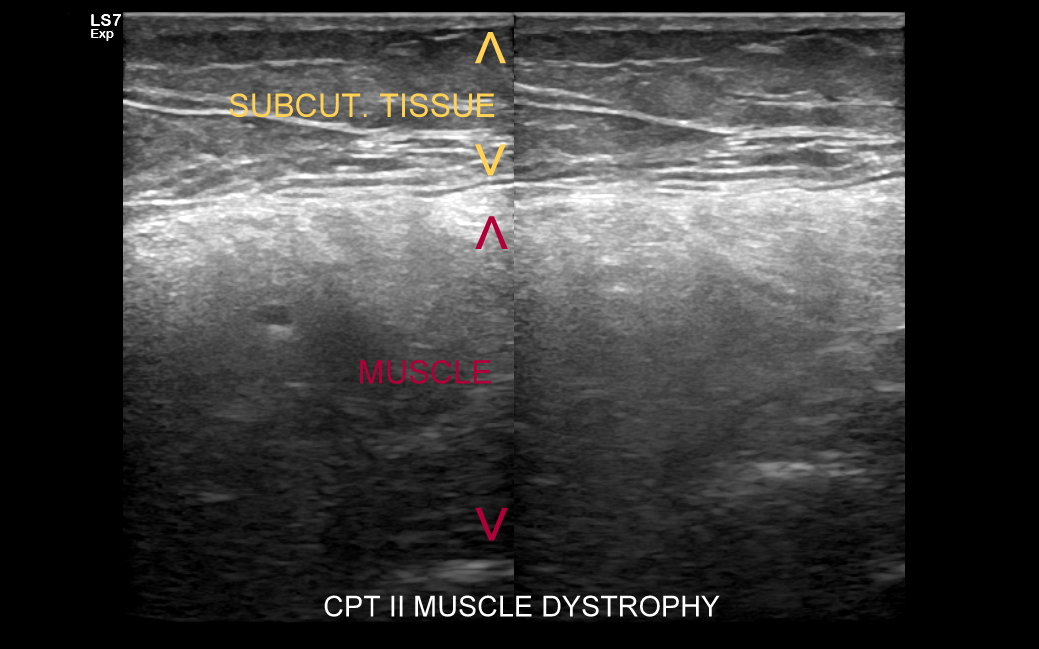

W skład układ ruchu, nazywanego także układem mięśniowo-szkieletowym, wchodzą takie struktury jak kości, ścięgna, mięśnie, stawy, więzadła, więzozrosty, troczki, pochewki ścięgniste, kaletki, chrząstki szkliste i chrząstki włókniste, nerwy, powięzie, a także naczynia krwionośne i chłonne. Badania obrazowe układu ruchu obejmują badanie rentgenowskie (RTG), tomografię komputerową (CT), rezonans magnetyczny (MRI) oraz badanie USG, nazywane także badaniem USG MSK (ang. musculoskeletal). Wszystkie wymienione są wobec siebie metodami komplementarnymi. Badania RTG oraz CT korzystniej obrazują kościec, z kolei MRI i USG tkanki miękkie, lecz nie jest to bezwzględną regułą. Wielokrotnie łączy się różnorodne metody diagnostyczne w celu dokładnej oceny patologii w układzie mięśniowo-szkieletowym. Omawiając temat należy poruszyć także kwestię narażenia na promieniowanie jonizujące, któremu organizm poddany jest podczas badań RTG i CT.

Jakie są więc zalety badania USG? Otóż jest ono szeroko dostępne, bezpieczne oraz ma przewagę nad innymi metodami diagnostycznymi w przypadku obrazowania tkanek płytko położonych i drobnych elementów (np. USG ręki, USG nadgarstka); przewagę w postaci możliwości wykonania prób czynnościowych w trakcie badania USG ortopedycznego, czy wykrywania stanu zapalnego w trakcie badania USG reumatologicznego. Badanie USG kości jest również bardzo czułą metodą do wykrywania drobnych złamań, pęknięć i przeciążenia kości! Czym różni się USG ortopedyczne od USG reumatologicznego? Kwestią nomenklatury oraz tym, iż to pierwsze koncentruje się na znalezieniu i ocenie urazu pośredniego lub bezpośredniego w układzie ruchu, a drugie na wykazaniu i ocenie stanu zapalnego.

Badanie USG w obrębie uda najczęściej wykorzystywane jest przy diagnostyce urazów sportowych, wśród których dominują naderwania mięśni. Naderwania u dorosłych lokalizują się zwykle w okolicy przyczepu bliższego mięśnia czworogłowego uda, przyczepów bliższych i dalszych tylnej grupy mięśniowej (mięśnie półbłoniasty, półścięgnisty, dwugłowy uda) określanej zbiorczo z języka angielskiego jako hamstringi, a także w obrębie mięśni przywodzicieli. W mięśniach uda nierzadko u młodych dorosłych pojawiają się nowotwory mięsaki. U dorastających dzieci naderwania w zakresie jednostek ruchowych występują na przyczepach ścięgnisto-chrzęstnych lub chrzęstno-kostnych.

USG łydki i podudzia najczęściej służy ocenie różnorodnych urazów, których sztandarowymi przykładami są łydka tenisisty, czy naderwanie / zerwanie ścięgna Achillesa. Dr Szczepański spotyka się w swojej praktyce również z szeregiem rzadkiego typu urazów i patologii takich jak przewlekły zespół ciasnoty przedziałów powięziowych, naderwania ścięgien zginaczy, przeciążenie troczków ścięgien, shin-splint, złamania przeciążeniowe kości, malformacje naczyniowe, zmiany nowotworowe, ciała obce, czy infekcje tkanki podskórnej, powięzi, a nawet mięśni.